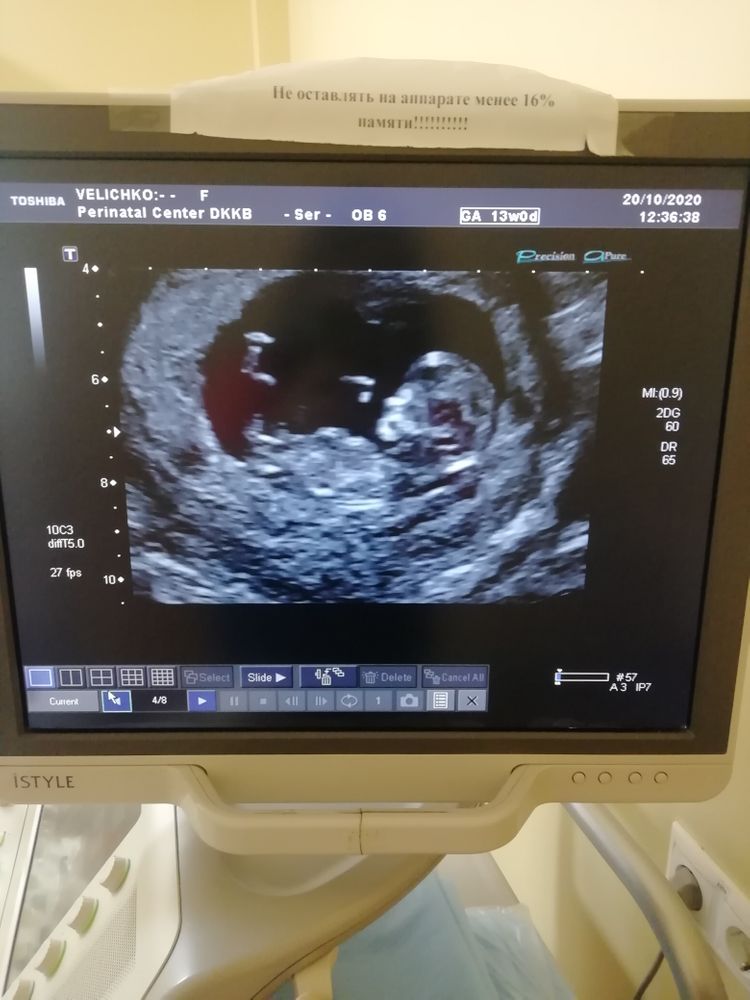

Добрый день девочки, подскажите как по фото определить пол малыша

Фото прилагаю

Определяют по наклону полового бугорка, потому что все остальное на этом сроке между ног выглядит одинаково)) Но для этого должно быть нормального качества фото и ракурс, с которого этот самый бугорок виден. По лбу, чсс и профилю - полнейшая чушь)

Да никак) каждая просто предположит настолько, насколько понимает в снимках УЗИ) я думаю мальчик) кто то по лбу определяет. Если я правильно понимаю,у вас 13 недель, то ещё рано для точного ответа) но врач может и сказать при хорошем аппарате)

С такого ракурса практически никак, сдайте анализ крови на определение пола если вам не терпится прям)

(((( Яночка и Николай Величко )))), ну тут сложно что-то разобрать, все размыто, если бы был ракурс "попа снизу" тут еще можно рассмотреть и если у вас срок на фото до 13-14 недель не врачи вряд ли вам что-то скажут

Анна К., срок был 11,5 врач сказала, что очень похоже на девочку, это вторая беременность